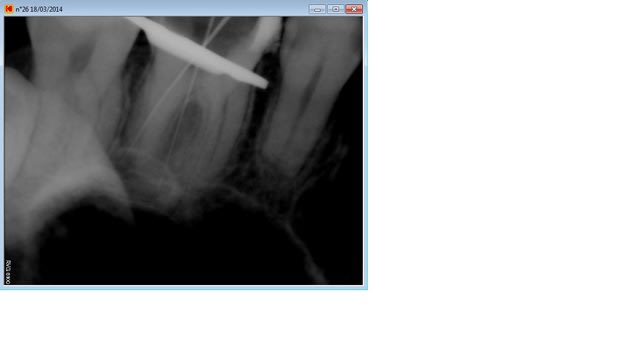

En voila deux supplémentaires, impossible de retrouver la dernière j'ai du l'enregistrer sur un autre dossier, je cherche ça.

On voit bien le cône dans le palatin qui bloque..

A vrai dire c'est surtout le palatin qui me gêne au niveau longueur, je trouve les deux autres pas trop mal (mis a part la condensation que je trouve encore très moyenne..)